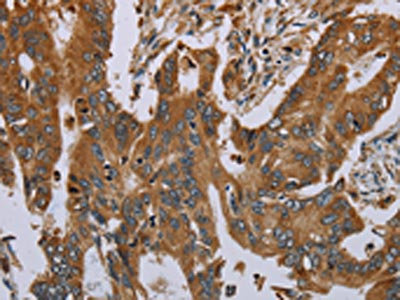

• The image on the left is immunohistochemistry of paraffin-embedded Human cervical cancer tissue using CSB-PA934414(OSM Antibody) at dilution 1/30, on the right is treated with synthetic peptide. (Original magnification: ×200)

• The image on the left is immunohistochemistry of paraffin-embedded Human colon cancer tissue using CSB-PA934414(OSM Antibody) at dilution 1/30, on the right is treated with synthetic peptide. (Original magnification: ×200)